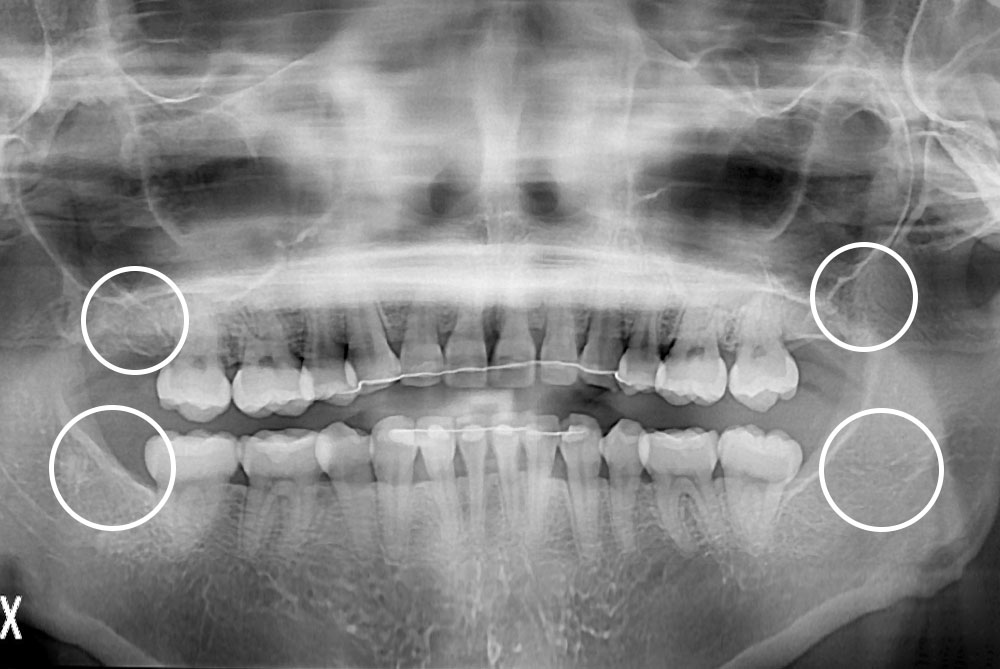

[사랑니] 매복 사랑니 발치

치료후 : 2021-03-08